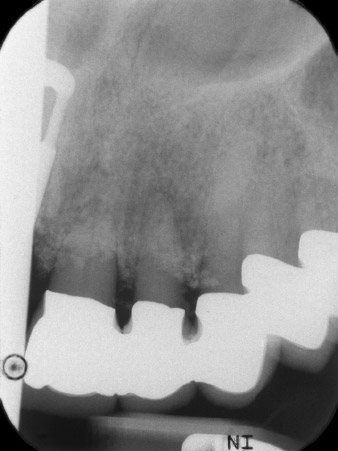

premières radios

Fig. 1 : Les premières radios ont révélé une restauration par couronne jumelée à remplacer. Une fois la restauration retirée, les dents 21 et 22 ont involontairement été extraites en même temps.

La radio a révélé une perte osseuse horizontale autour des dents 21 et 22 (Fig. 1). Lorsque la structure de couronne a été retirée, ces dents ont involontairement été extraites en même temps.